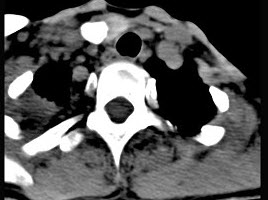

女,16岁,发现左颈部肿块两年,CT如图